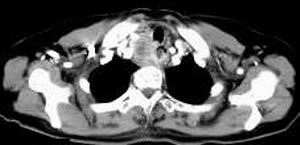

女,61岁,吞咽困难(包括开水)已久。

食道中上段癌并锁骨上窝淋巴结转移.

1、同意食道上段ca併淋巴结转移。

3、右侧甲状腺是否有问题?是否甲状腺ca转移食道上段。因为肿块顶部图像没有,请楼主展示,谢谢!

食道中上段中分化鳞癌伴锁骨上淋巴结转移